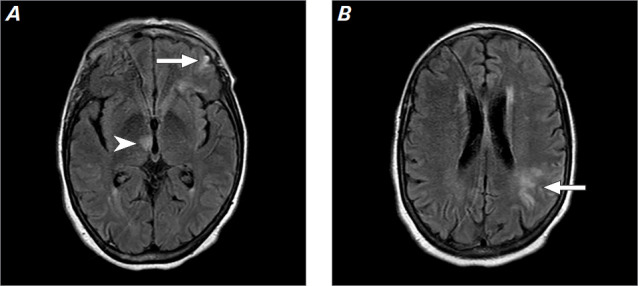

Cardiac myxomas are a rare phenomenon within the general population, and although there are reports of them, giant myxomas are not common in the medical literature. This report presents a case of a giant left atrial cardiac myxoma in a 57-year-old female patient who was largely asymptomatic until she presented with a diffuse thromboembolic stroke. This case report highlights the importance of surgical management of cardiac myxomas and discusses the difference in open vs minimally invasive surgical resection of giant cardiac myxomas.

Abstract Image